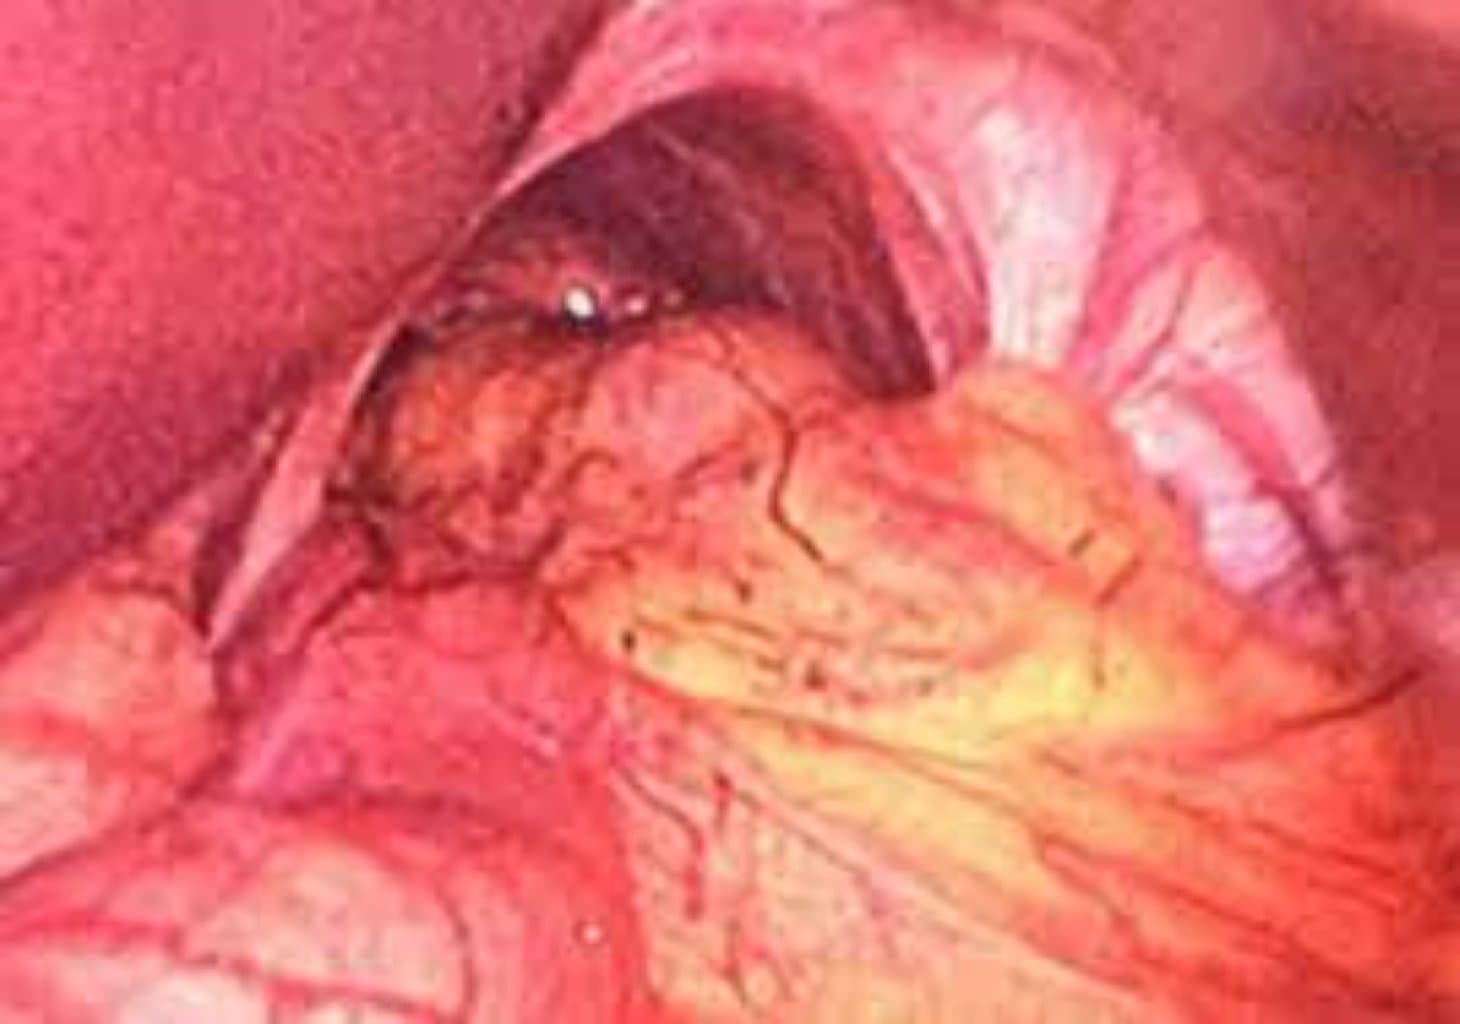

| Endoskopi (Ezofagoskopi) | Qarın boşluğunun və daxili orqanların vizual müayinəsinə imkan verir. |

Lakin daha ciddi və ağır hallarda cərrahi əməliyyat qaçılmazdır. Cərrahi müdaxilə vasitəsilə diafragma yırtığı bərpa edilir və orqanların normal anatomik mövqeyi təmin olunur.